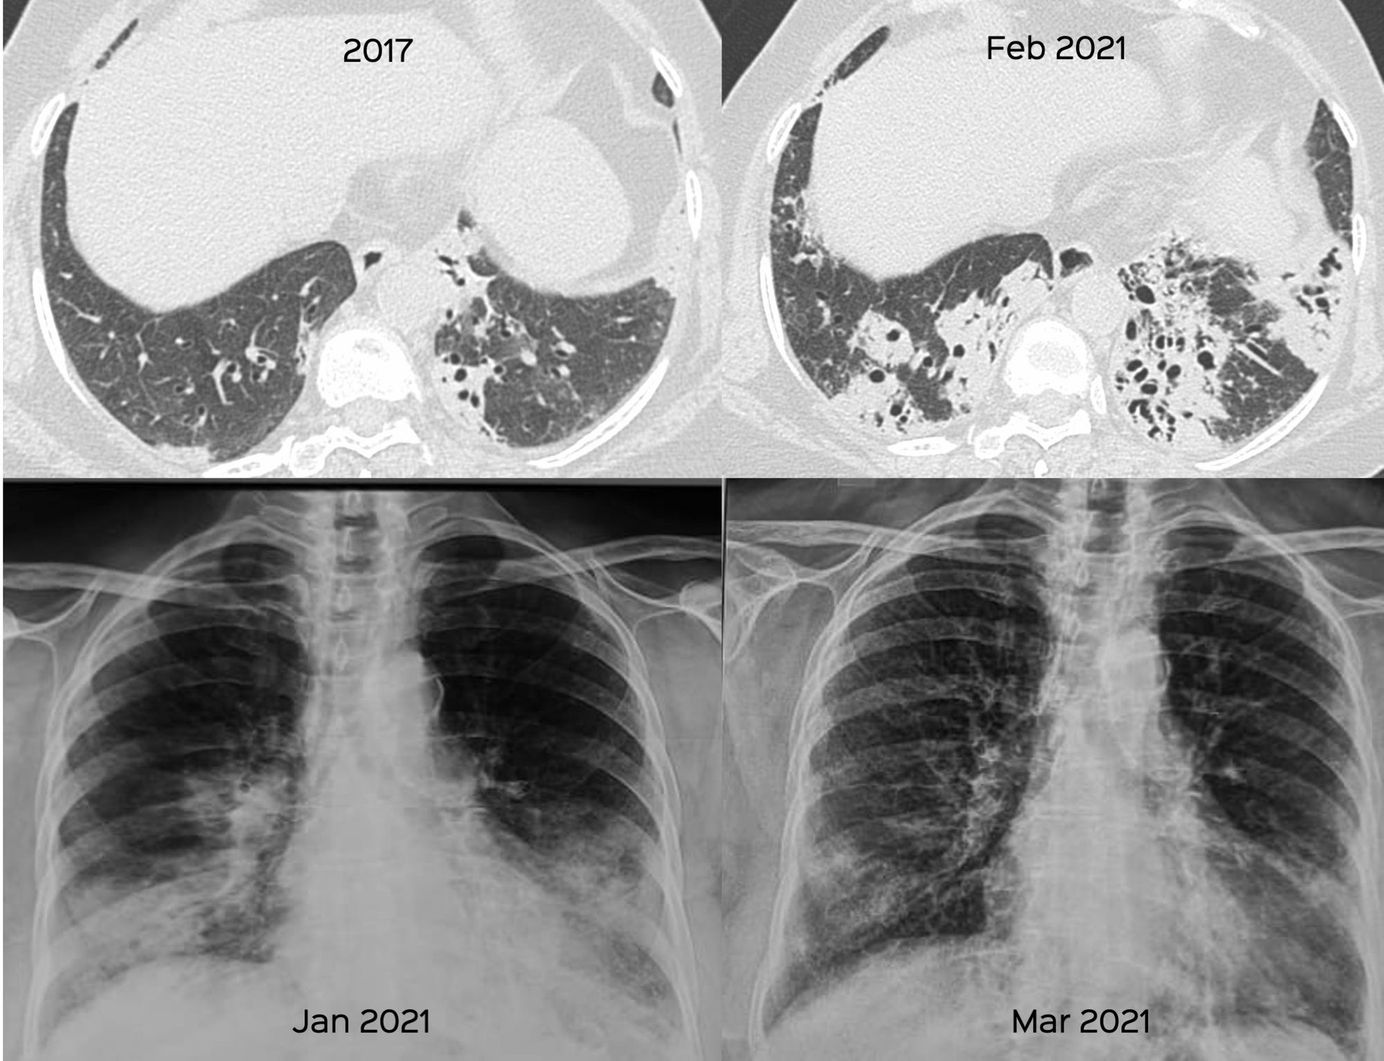

Case 10: Non-Resolving Progressive Opacities, Organizing Pneumonia and a Diagnosis After 3 Years Members Public

67-years old lady who presented in 2017 with an organizing pneumonia (OP) pattern, and then 3 years later with significant progression

Bhavin Jankharia

Interstitial Lung Disease